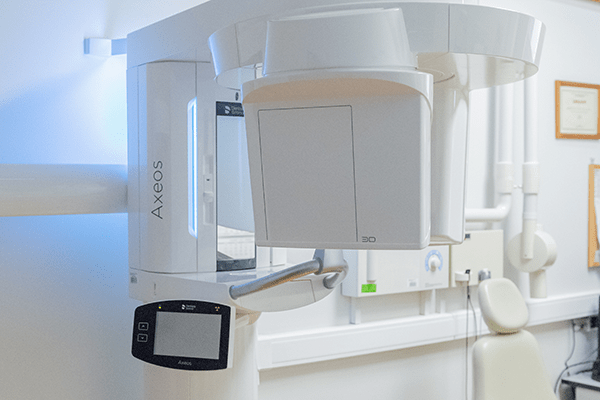

Фотографии и изображения КТ аппарата ORTHOPHOS SL